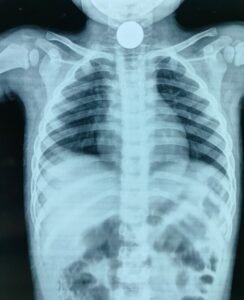

चम्पावत : शनिवार की सुबह चम्पावत के एक परिवार के लिए अचानक घबराहट और बेचैनी से भरी साबित हुई। खेलते-खेलते...